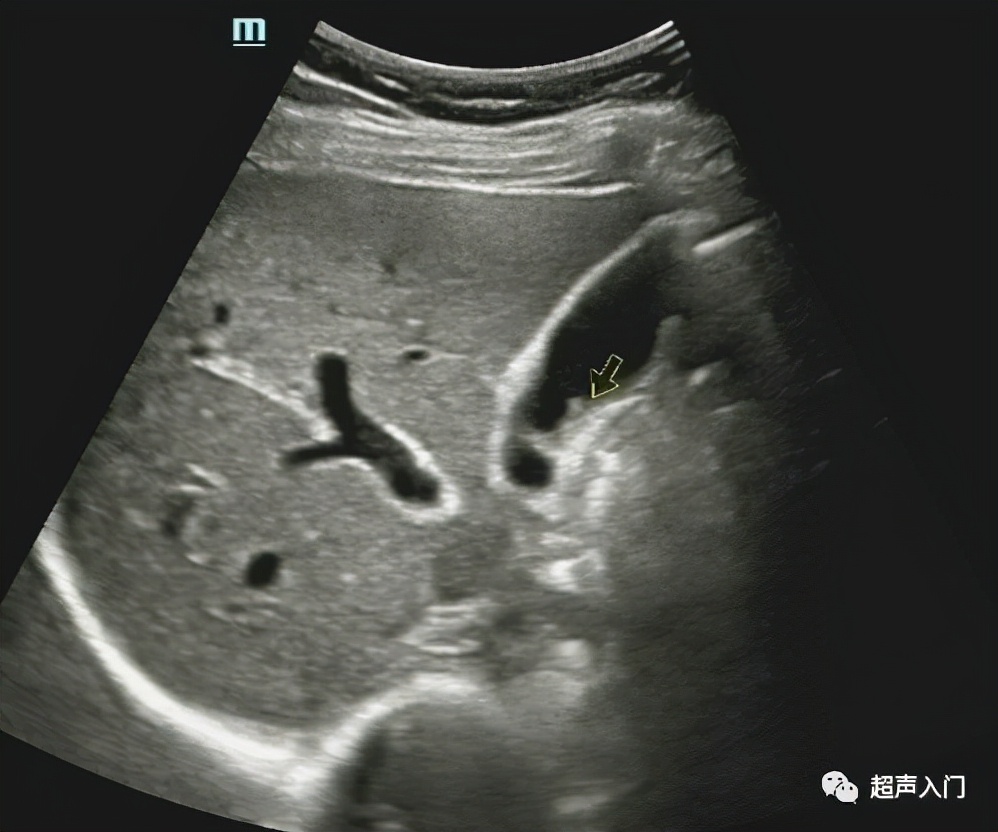

08 胆囊息肉

(胆囊上的肉疙瘩)